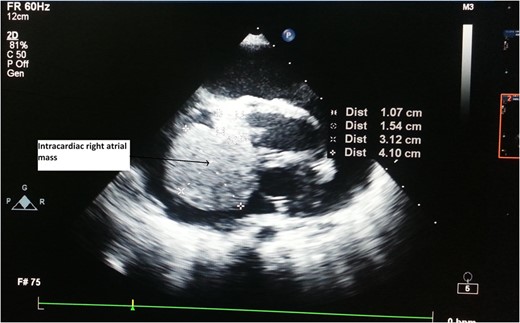

Primary cardiac tumour is a rare entity as secondaries in the heart are more common. A 2-year-old child was having repeated respiratory tract infection with poor oral intake and poor activity for 3 months. His symptoms progressed from New York Heart Association (NYHA) Class II to IV. On evaluation he had an intracardiac mass with extracardiac extension. Emergency tumour excision under deep hypothermic circulatory arrest was performed with provisional diagnosis of sarcoma. But Serum markers, histopathological examination and immunohistochemistry confirmed diagnosis of yolk sac tumour. Postoperative recovery was uneventful and the child was receiving adjuvant chemotherapy. Extensive literature review revealed only four cases of primary intracardiac yolk sac tumour published till date. Our case report is unique, in that intracardiac tumour had extracardiac extension by infiltration through right atrial wall. Previous four reports mention purely intracardiac mass.

A 2-year-old male child was brought to hospital with respiratory distress since last 2 weeks. He was having repeated respiratory tract infection since last 3 months along with poor oral intake and poor activity. His symptoms progressed from New York Heart Association (NYHA) Functional Class II to IV over last 2 weeks. On investigation at another hospital he was diagnosed with intracardiac mass having extracardiac extension. Parents brought the child to our hospital for further management.

CT Thorax showing intracardiac right atrial mass with extracardiac extension.